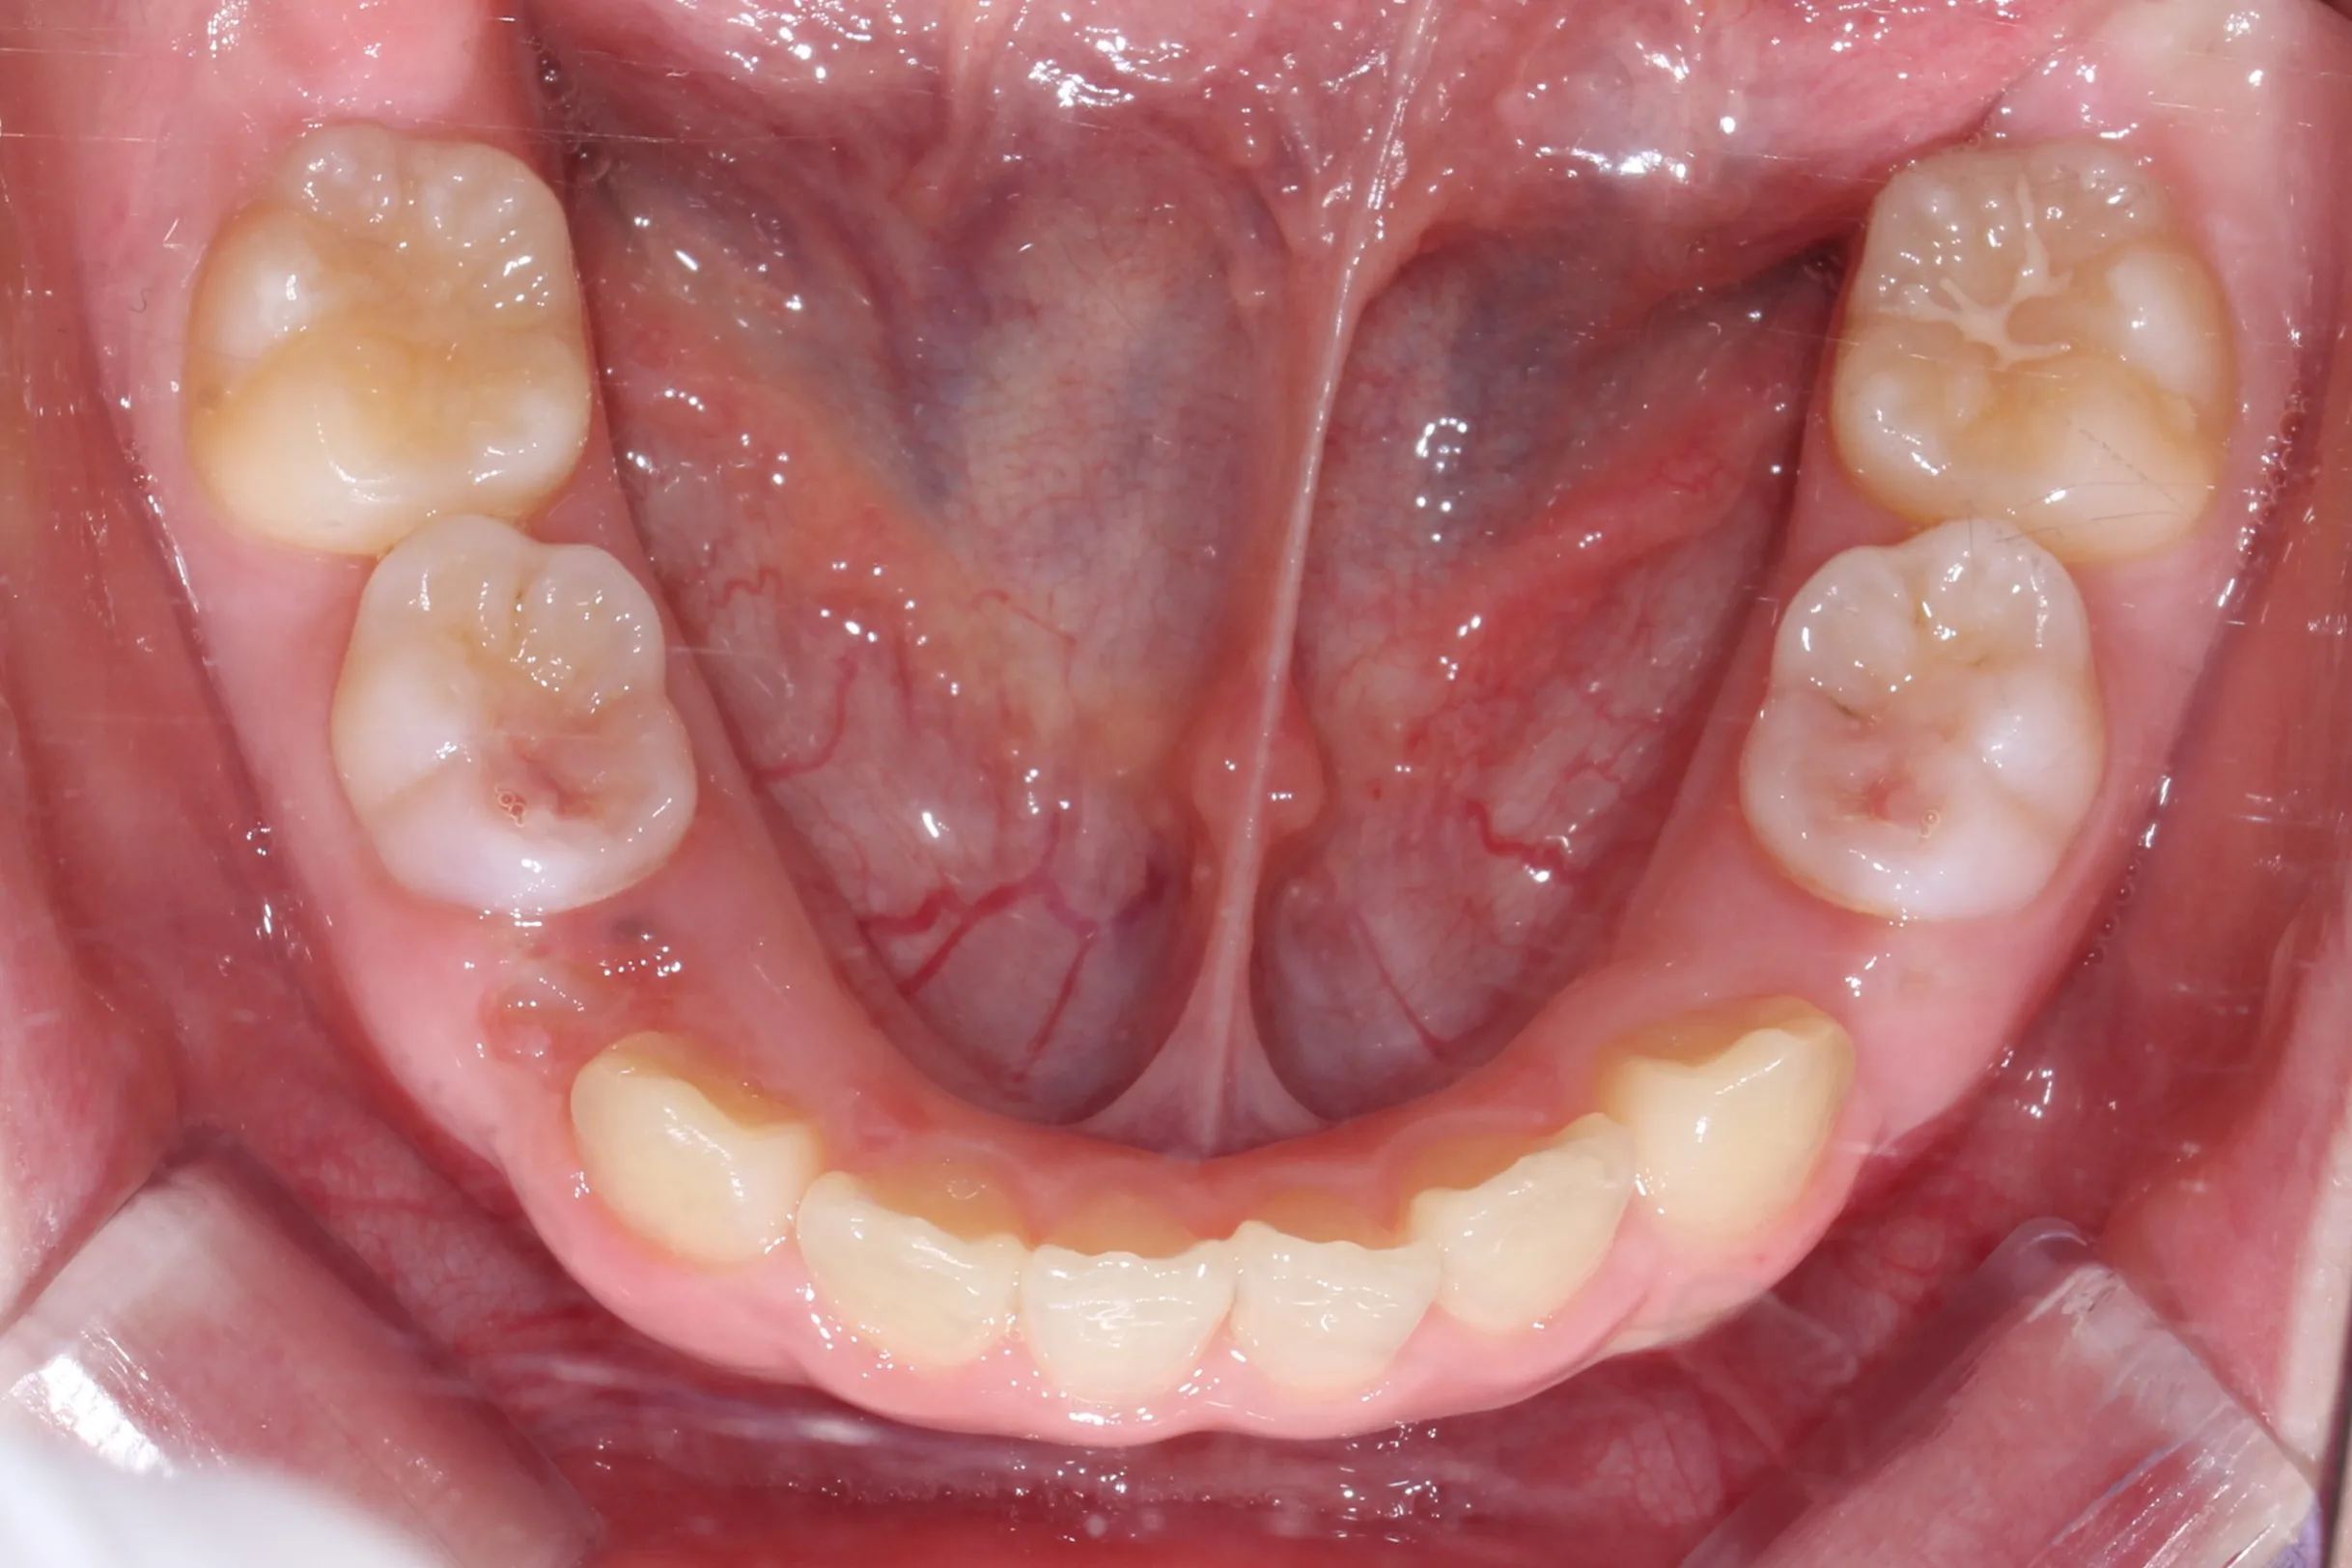

만 11세 환자분께서 튀어나온 앞니와 다물어지지 않는 입술 때문에 내원하셨습니다. 검진 결과 상악 전돌을 동반한 2급 부정교합(Class II malocclusion) 상태였으며, 아래턱의 성장이 다소 부족하여 골격적인 조화가 필요한 상황이었습니다.

이번 치료에는 인비절라인 퍼스트(Invisalign First)에 하악 전방 견인(Mandibular Advancement, MA wing)을 추가하여 치료를 진행하였습니다. 성장기라는 시기적 특성을 적극 활용하여 아래턱의 점진적인 성장을 유도하고, 과도한 상악 전치부 돌출을 개선하는 데 치료의 핵심 전략을 두었습니다.

2년 7개월의 치료 과정을 거치며 환자분의 협조도 덕분에 안모 프로파일과 교합이 안정적으로 개선되었습니다. 성장기라고 해서 무조건 교정이 어려운 것은 아닙니다. 적절한 시기에 맞춤형 장치를 선택한다면 골격적 불균형을 효과적으로 바로잡을 수 있습니다.